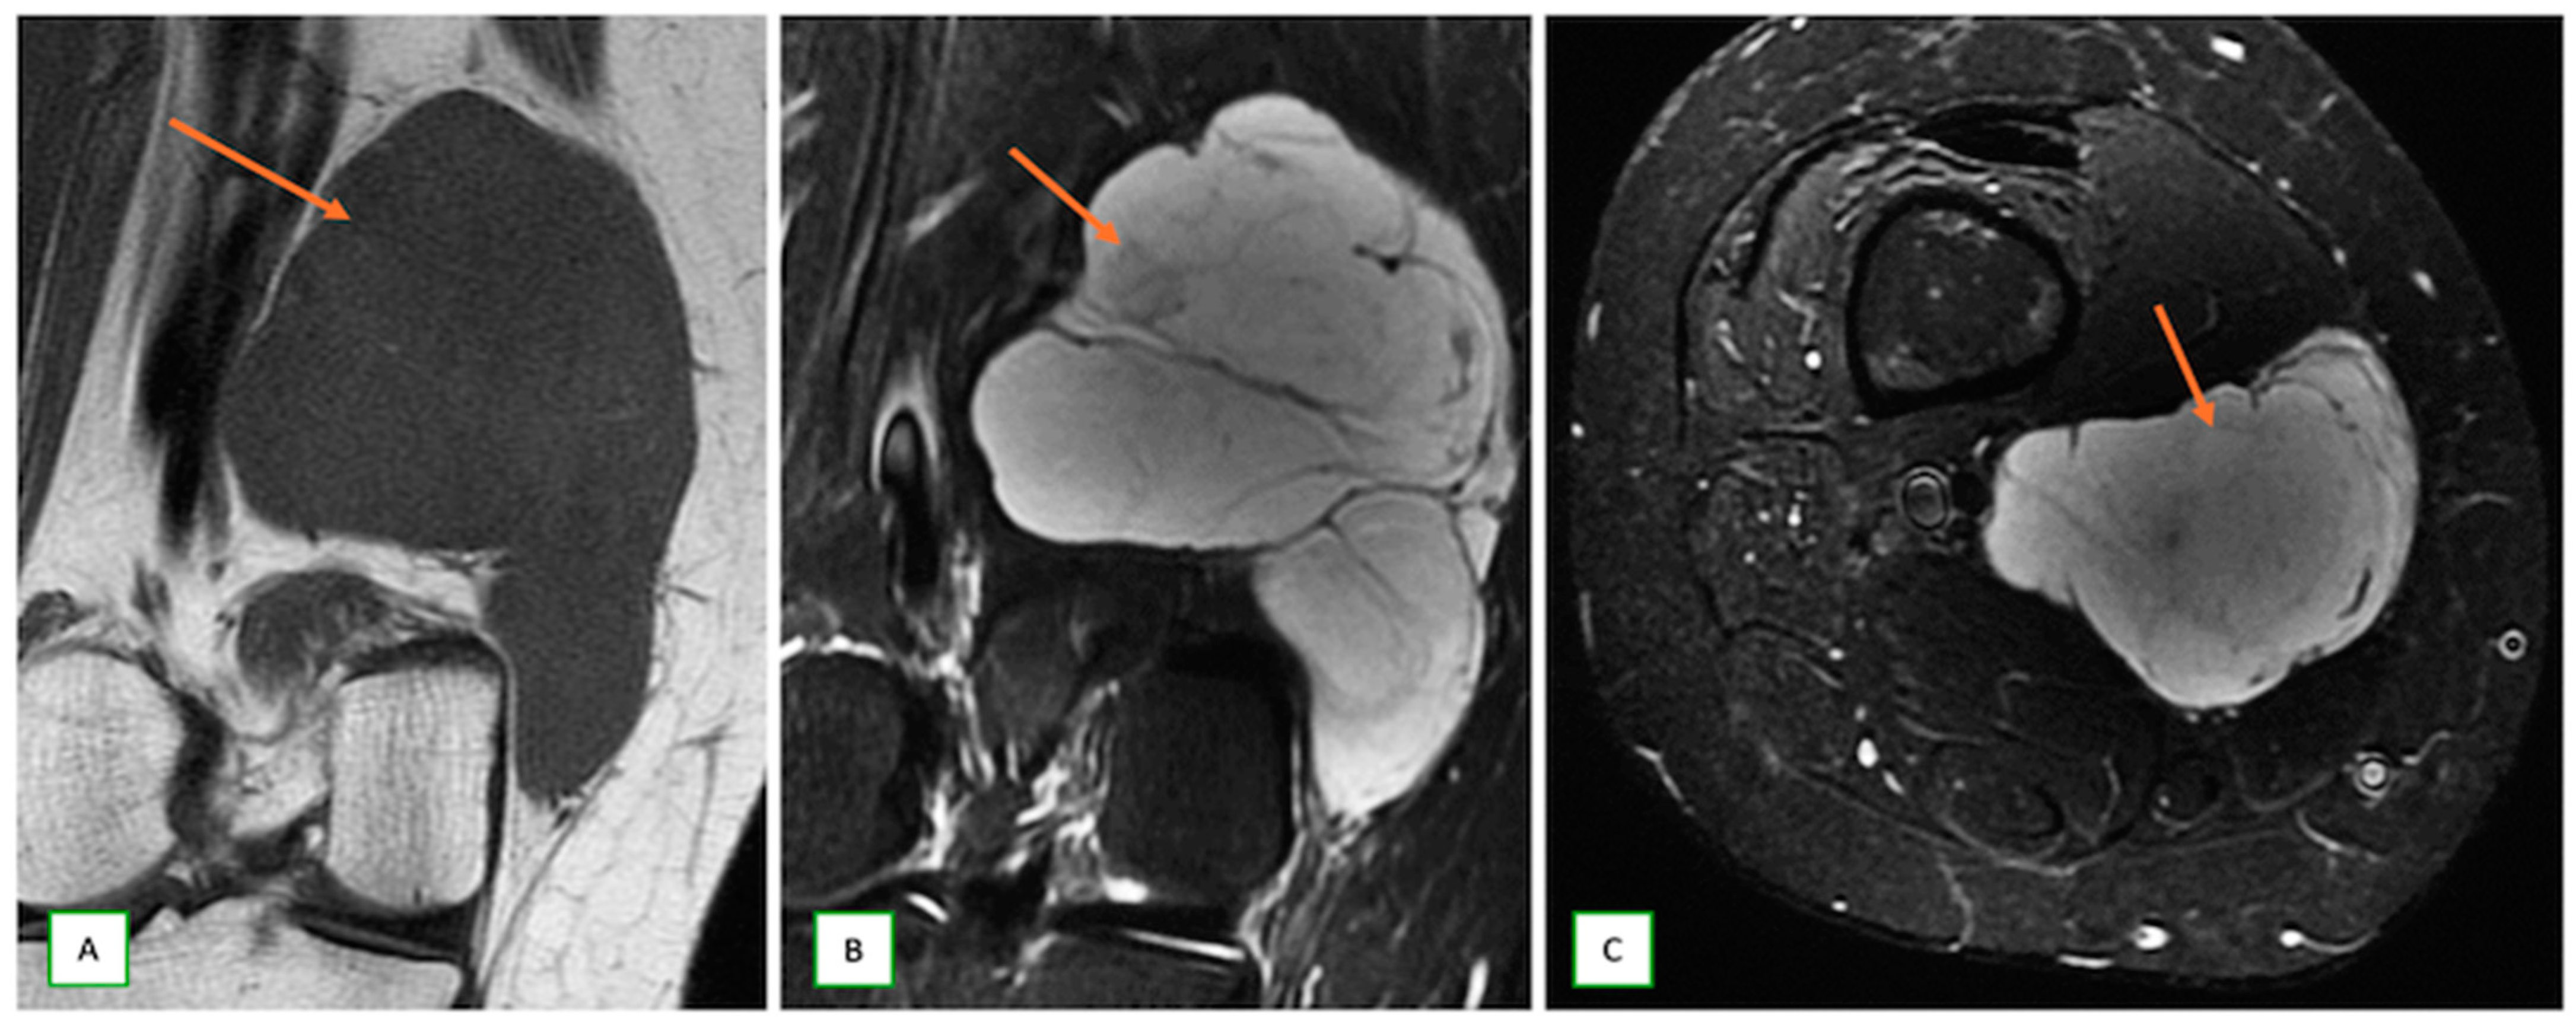

- Dermal nerve sheath myxomas or neurothekeomas occur as small, painless nodules in young adults; they appear hypoechoic on USG and markedly hyperintense on T2-w images (Figure 14).